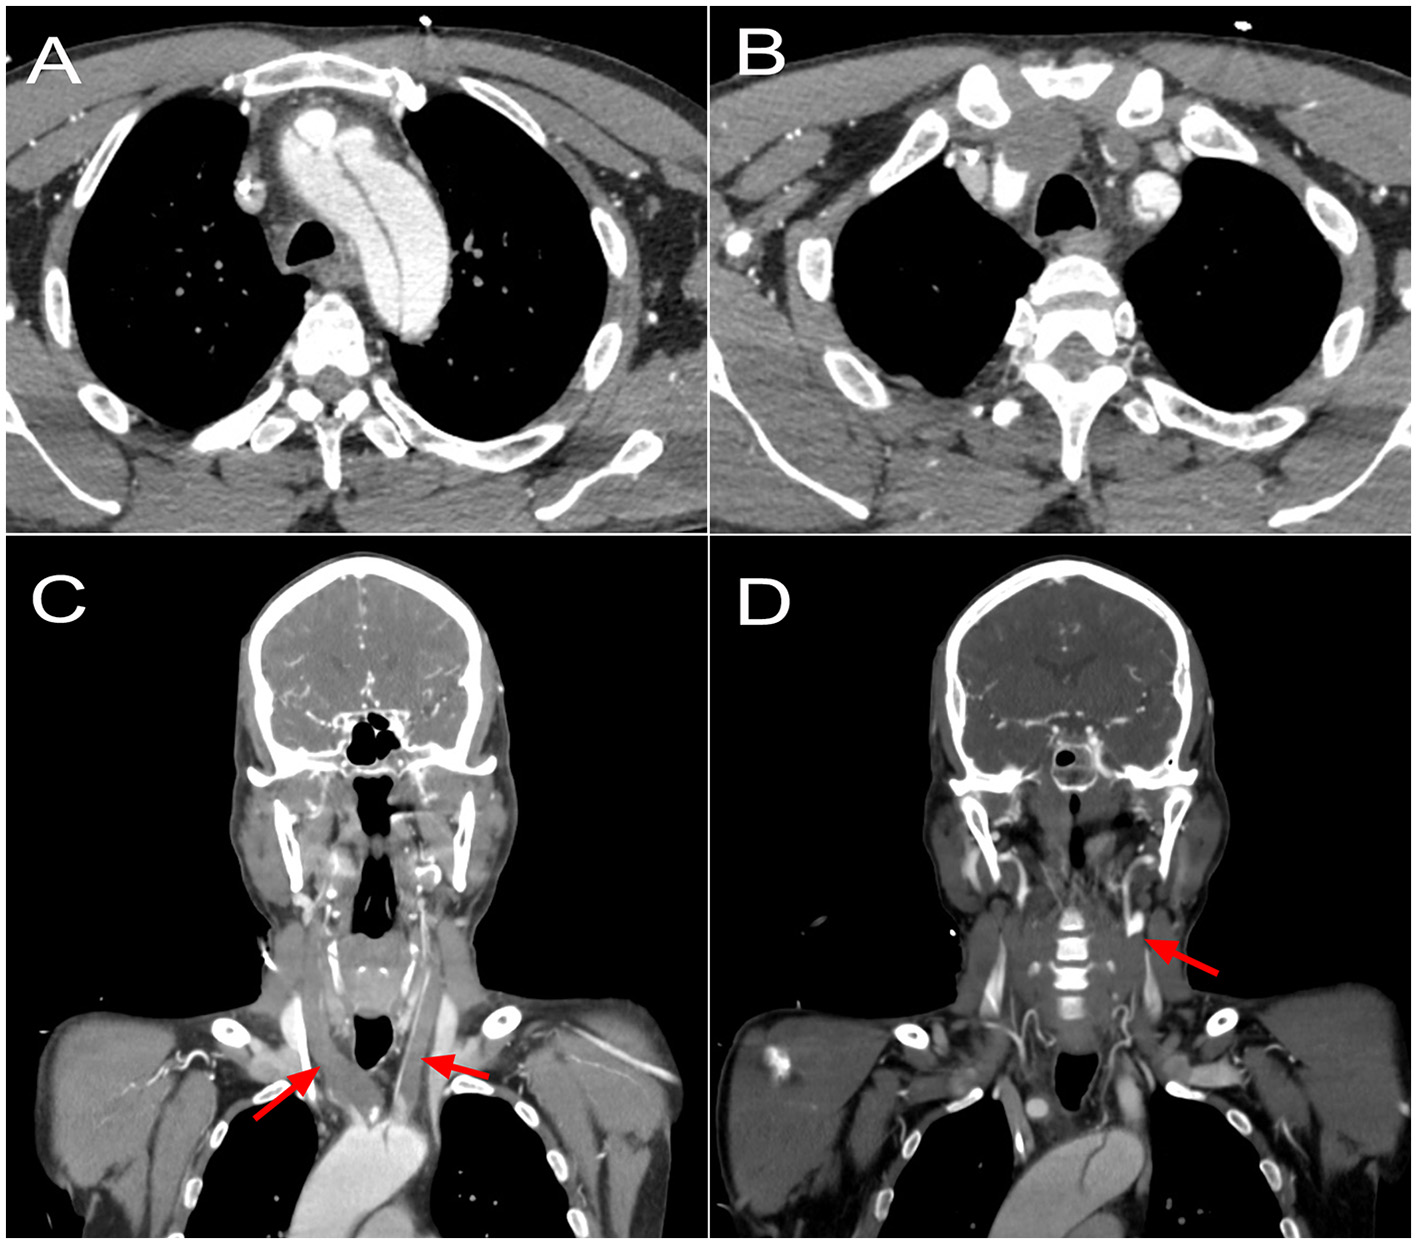

A 48-year-old male with no known medical history and no family history of aortic disease or connective tissue disorders was admitted to a secondary Regional Hospital due to paresis of the lower right extremity. CT scan showed a TAAD starting at the proximal aortic arch and extending to the left internal iliac artery. All three supra-aortic vessels were compromised, with occlusion of both carotid arteries. The patient was transferred to our center for emergent surgery. The patient arrived at our center (1.5-h flight) in a deep stupor (Glasgow coma scale of 8) and with right hemiparesis (MRC strength scale of 1). A repeated CT showed a complete occlusion and thrombosis of the right common and internal carotid artery. The left common carotid artery was also occluded and thrombosed, showing recovered flow just before the bifurcation (Figure 1). The left subclavian artery was dissected, with involvement of the vertebral artery origin. There were no signs of consolidated cerebral infarction on CT. A GERAADA score (5) of 28.7% mortality at 30-day was calculated. Although its neurological prognosis was uncertain, there were no categorical elements of poor prognosis if cerebral circulation was restored. For this reason, we decided to proceed with emergency surgery.

Figure 1. Preoperative CT scan showing (A) an acute type A dissection compromising the aortic arch and origin of supra-artic vessels. (B) A complete occlusion of the brachiocephalic trunk, with reperfusion of the right subclavian artery; a complete occlusion of the left common carotid artery; a dissected left subclavian artery. (C) A coronal reconstruction showing complete occlusion of both common carotid arteries since origin at the aortic arch (arrows). (D) A coronal reconstruction showing reperfusion at the level of the left carotid bifurcation (arrow).